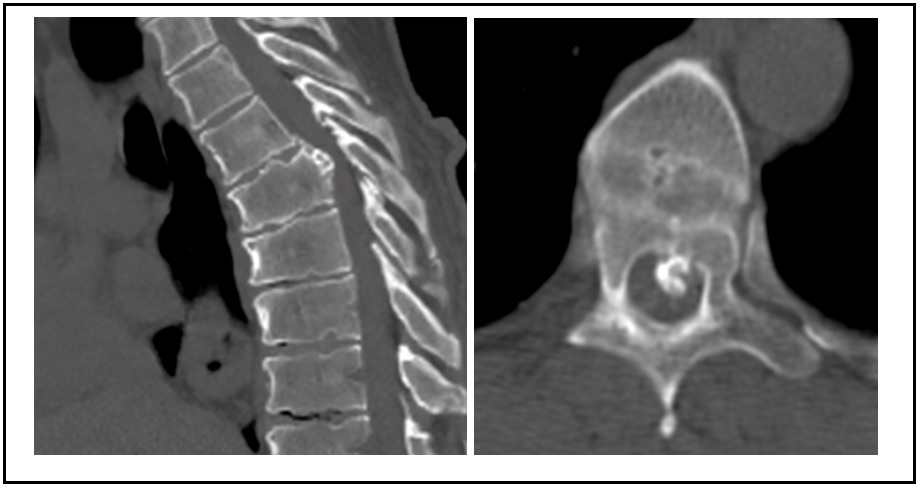

Existen múltiples técnicas para la descompresión medular en la columna torácica, cada una con sus ventajas y desventajas y con distintos requerimientos de destrezas quirúrgicas. Se han desarrollado técnicas mínimamente invasivas que disminuyen las tasas de morbilidad, con buenos resultados funcionales. Se presenta el caso de un hombre de 64 años, con clínica de compresión medular, una hernia de disco central, calcificada a nivel del quinto disco torácico, migrada hasta el borde inferior de la sexta vértebra torácica, con franca compresión medular. Se realizó un abordaje lateral transpleural mínimamente invasivo, con una corpectomía parcial posterior de la sexta vértebra, sin fijación adicional. El paciente tuvo una buena evolución, sin progresión del cuadro neurológico ni dolor costal residual. Los abordajes laterales mínimamente invasivos son técnicas válidas para tratar patologías compresivas de la columna torácica, con bajas tasas de morbimortalidad y una rápida recuperación. Abstract There are multiple techniques for spinal cord decompression in the thoracic spine, each with its advantages and disadvantages, and requiring different surgical skills. Recently, minimally invasive techniques have been developed, reducing morbidity rates and achieving good functional results. We present the case of a 64-year-old male with spinal compression symptoms, central disc herniation calcified at the fifth thoracic vertebra, which migrated to the lower end of the sixth thoracic vertebra. Diagnosis was clear for spinal cord compression. Partial posterior corpectomy of the sixth vertebra was performed with a minimally invasive transthoracic transpleural lateral approach and without additional fixation. The patient had a good outcome on follow-up, without progression of neurological symptoms or residual rib pain. Minimally invasive lateral approaches are valid techniques for the treatment of compression disorders of the thoracic spine, with low rates of morbidity and mortality, and a rapid recovery.Descargas